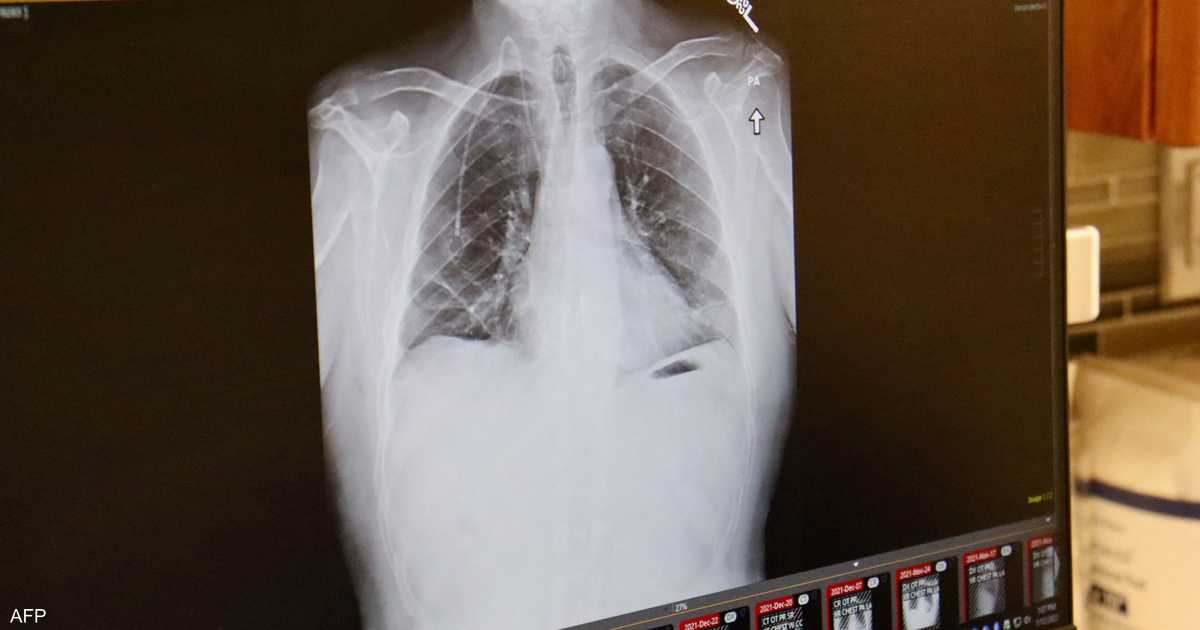

سرطان الرئة يصيب غير المدخنين

ارتبطت الإصابة بسرطان الرئة منذ عقود بالتدخين، لكن زيادة نسبة الإصابة بهذا المرض لدى غير المدخنين دفع عدد من العلماء لتصنيفه كمرض مستقل يختلف عن فئات السرطان المعروفة سابقا، وله خصائص تميزه.